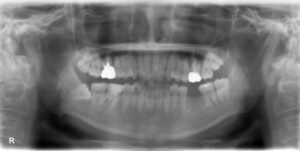

下顎前歯1本・臼歯3本欠損症例

BEFORE AFTER 54歳女性/下4本欠損/インプラント埋込手術 【治療内容】 右下中切歯の歯周病が重度まで進行し…